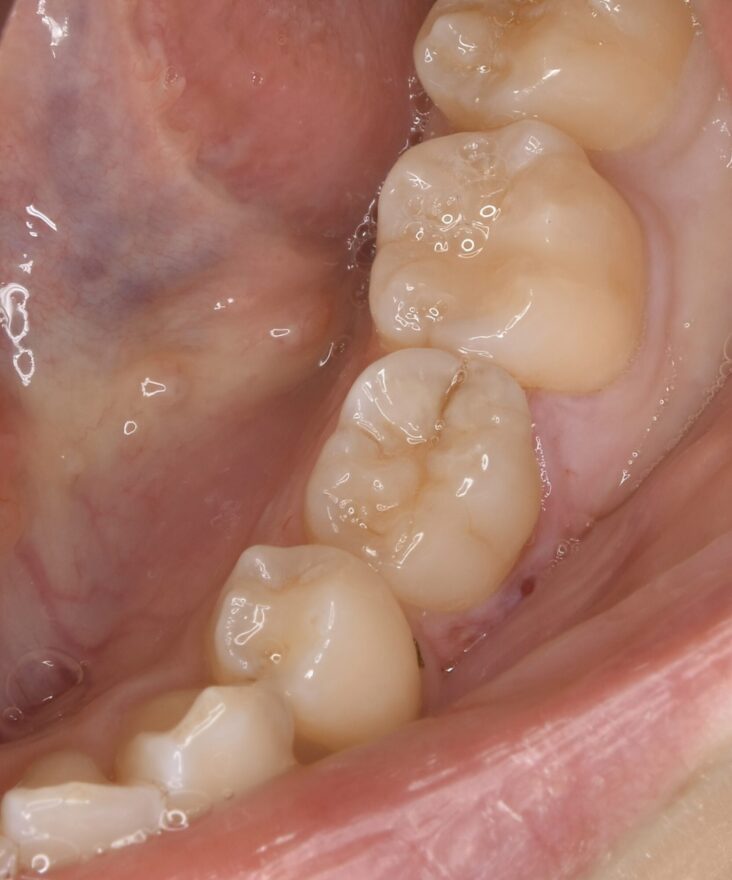

初診時の口腔内写真

上下の歯列の真ん中(正中)が合っていません。

この方向から見ると、前歯が出ていることが分かります。

乳歯の根本が腫れています。

前歯のガタガタが気になります。